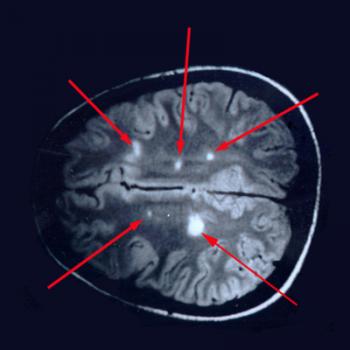

- МРТ сосудов головного мозга.